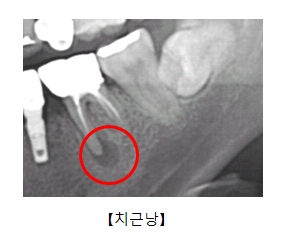

치근낭은 여러 원인에 의해 치아의 뿌리 끝에 물혹이 발생한 질환을 의미합니다.

치근낭의 원인은 심한 충치 등으로 인해 치아가 뿌리 끝까지 손상되어 치아 뿌리 끝에 있는 염증이 물혹으로 변화한 것입니다.

방사선 사진을 촬영해 보면 뿌리 끝에 경계가 선명한 주머니가 달려 있는 것을 볼 수 있습니다.